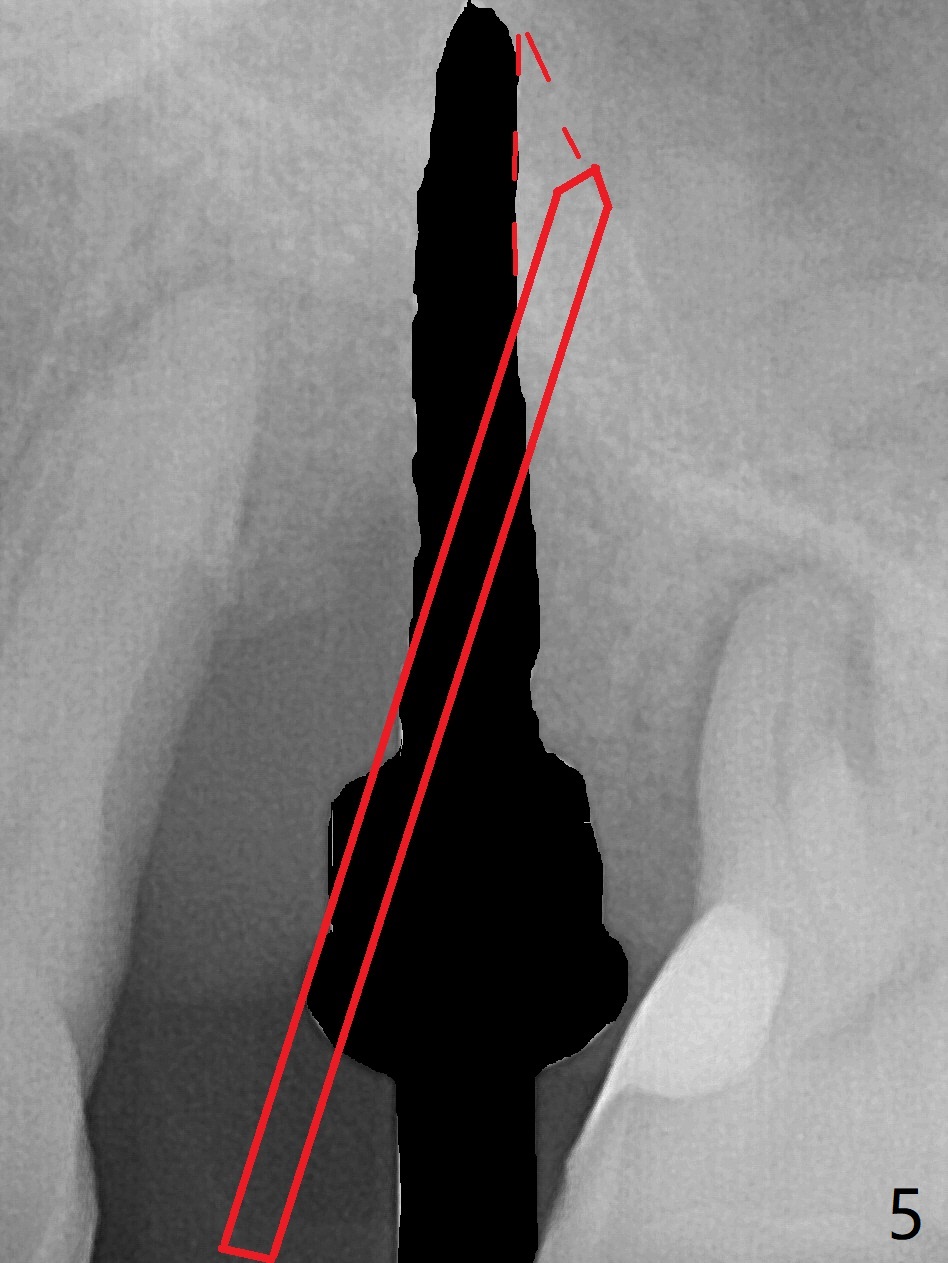

There is more bone apical to the residual root at #13 (Fig.1 red line). An immediate implant along the long axis of the root can be longer, 11.5 mm, favorable for primary stability (Fig.2 (CT taken immediately preop)). The initial trajectory is not ideal (Fig.3). When the pointed/Lindamann bur is removed (Fig.4), effort is made to move the apical end of the osteotomy distal (Fig.5 red arrow) by removing the apical bone (red dashed line). Following sequential osteotomy, a 4x10 mm dummy implant is placed with the trajectory remaining not so ideal (Fig.6,7). As the dummy implant is removed (Fig.8), a new osteotomy is established distal to the existing one (Fig.9). Subsequent drills gradually shift into the original osteotomy (Fig.10 red arrow). When the same dimension dummy implant returns, the trajectory improves with decreased stability (Fig.11). It seems reasonable to place a larger implant without further osteotomy. After placing PRF membrane and Vanilla graft for sinus lift (Fig.13 *), a 4.5x10 mm definitive implant is placed with loss of control in the trajectory (Fig.12,13).

When the initial osteotomy is off substantially (Fig.4), an osteotomy should be established de novo and as early as possible (Fig.14) so that subsequent osteotomy will not relapse to a great extent. More ideally, the initial osteotomy should be planned correctly (Fig.15,16) with sacrifice of the bone height. Nearly 1 month postop, the 4.5x5.5(5) cementation abutment is loose. When it is removed, the patient feels pain from the implant. A 5.5x6 mm healing abutment is placed instead. The implant osteointegrates with trabecular pattern in the sinus 9 months postop (Fig.20 *). The gingiva around the crown at #13 is healthy 1 year 4 months post cementation (Fig.18). Check the distal surface of #13 for bone loss if the tooth #14 is to be extracted.